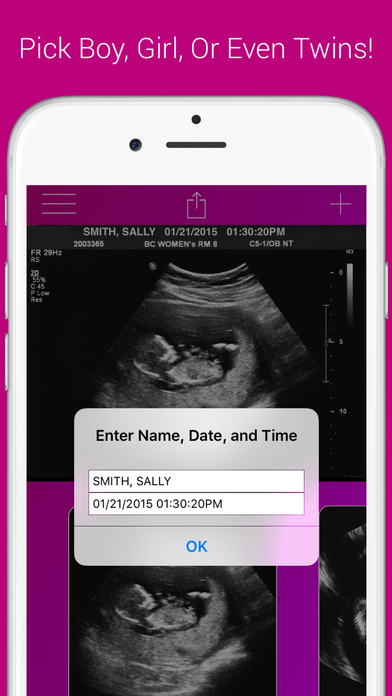

3. Ultrasound Pregnancy Prank

Aplikace hlavně pro ženy a dívky Vygeneruje vám snímek z ultrazvuku, kde je jasně vidět, že jste těhotná. Dokonale tak můžete vystrašit svého partnera, ovšem v některých případech i potěšit. Samozřejmě ji mohou využít i muži a to tak, že své přítelkyni/manželce pošlou snímek z ultrazvuku své „milenky“ s doplňujícími informacemi, jak se to vše vlastně stalo.